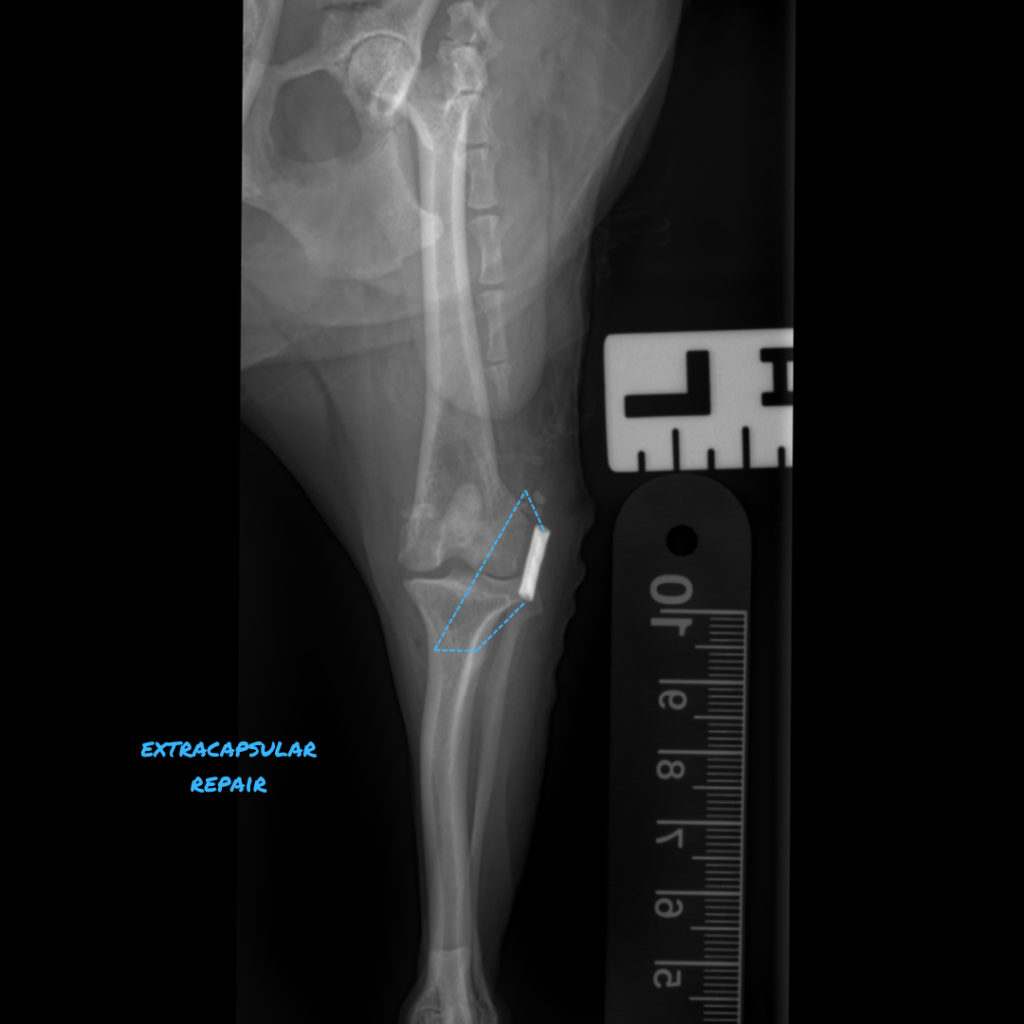

The Extracapsular Lateral Suture Technique uses a synthetic, monofilament or braided polyethylene material to address cranial tibial subluxation (Blue dotted line). However, these extracapsular sutures are not designed for permanent stabilization, as they eventually fail over time. The objective is for the suture to remain functional for 8-12 weeks, facilitating the development of periarticular scarring and allowing for sufficient muscular rehabilitation to stabilize the joint.